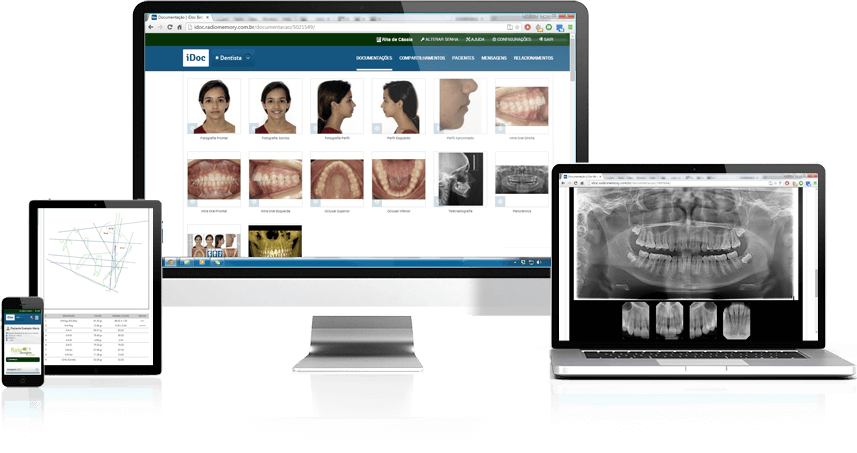

*Entregas virtuais por site e aplicativo iDoc

Entregas físicas por impressões em PELÍCULA ou Papel FOTOGRÁFICO

*Entregas virtuais por site e aplicativo iDoc

Entregas físicas por impressões em PELÍCULA ou Papel FOTOGRÁFICO